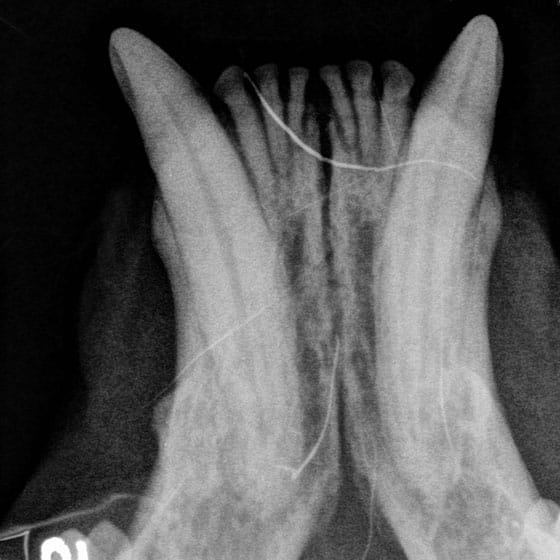

Dental Radiographs (X-rays):

- X-rays are crucial for diagnosing issues not visible to the naked eye, such as tooth root abscesses, bone loss, or retained roots. They guide our treatment plan for optimal outcomes.